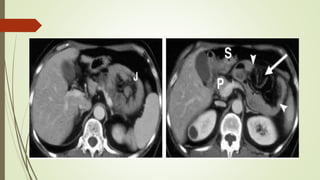

HERNIA DIRECTA

 Pasa anteromedial a vasos epigástricos inferiores

 Masa lateral a músculo recto

 «Signo lateral cresciente»

 CI desplazado y comprimido lateralmente, incluyendo grasa y demás

contenidos

HERNIA INDIRECTA

 Pasa superolateral a vaso epigástrico inferior  lateral y medial

siguiendo el CI

 Se muestra con el contenido habitual del CI, no se comprime ni

distorsiona